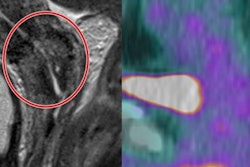

Integrated PET/MRI offers both synchronicity and synergism.

Integrated PET/MRI offers both synchronicity and synergism.Goh also discussed the advantages of whole-body pseudo CT, whereby MRI is used to develop a CT scan with Hounsfield units equivalent to a CT that is acquired in clinical practice.

This can then be leveraged to improve standardized uptake value (SUV) quantitation from bone, which is one of the issues with attenuation correction, she noted, as well as for radiotherapy planning in which there is an issue of dosing. Although it's early days, she pointed to great potential for this technique for prostate radiotherapy planning and gynecological cancers.